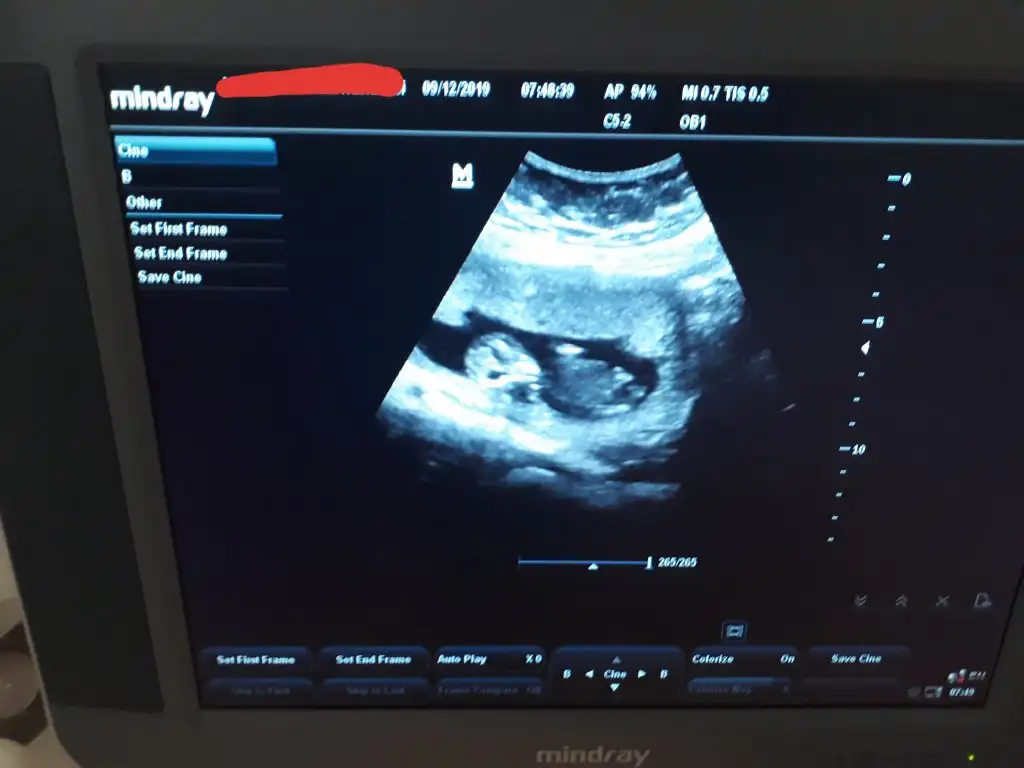

Kızlar geldik hastaneden 12+5 olmuşuz ense ölçümü burun kemiği herşey güzel dedi 2li test için kan aldı 1 hafta sonra çıkar dedi